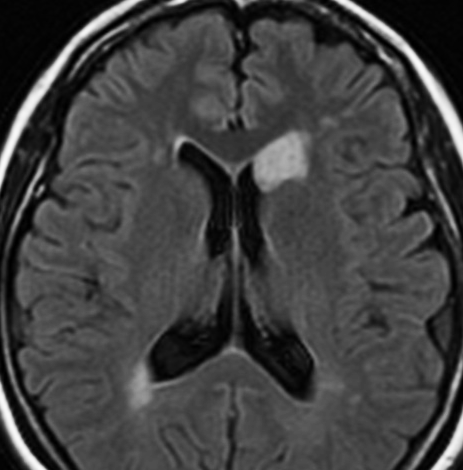

無症状で偶然発見された47歳女性の側脳室内上衣下腫

無症候で偶然発見された左側脳室前角尾状核頭に接したsubependymoma。定位脳生検で病理診断を得たましたが,3年間の観察で徐々に増大しました。左上が発見時,1年後(右上),2年後(左下),3年後(右下)

CTではやや低吸収,T1ガドリニウムでは低信号となりガドリニウム増強されません。小さな上衣下腫の場合は等吸収あるいは等信号のものも多いです。小さく点状に造影されている部分があるがこれは定位脳手術痕(track)です。

左中前頭回からの経皮室法 left middle frontal gyrus transcortical approach で全摘出できました(右図)。